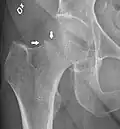

X-ray showing a suspected compressive subcapital fracture as a radiodense line

-

CT scan shows the same, atypical for a fracture since the cortex is coherent